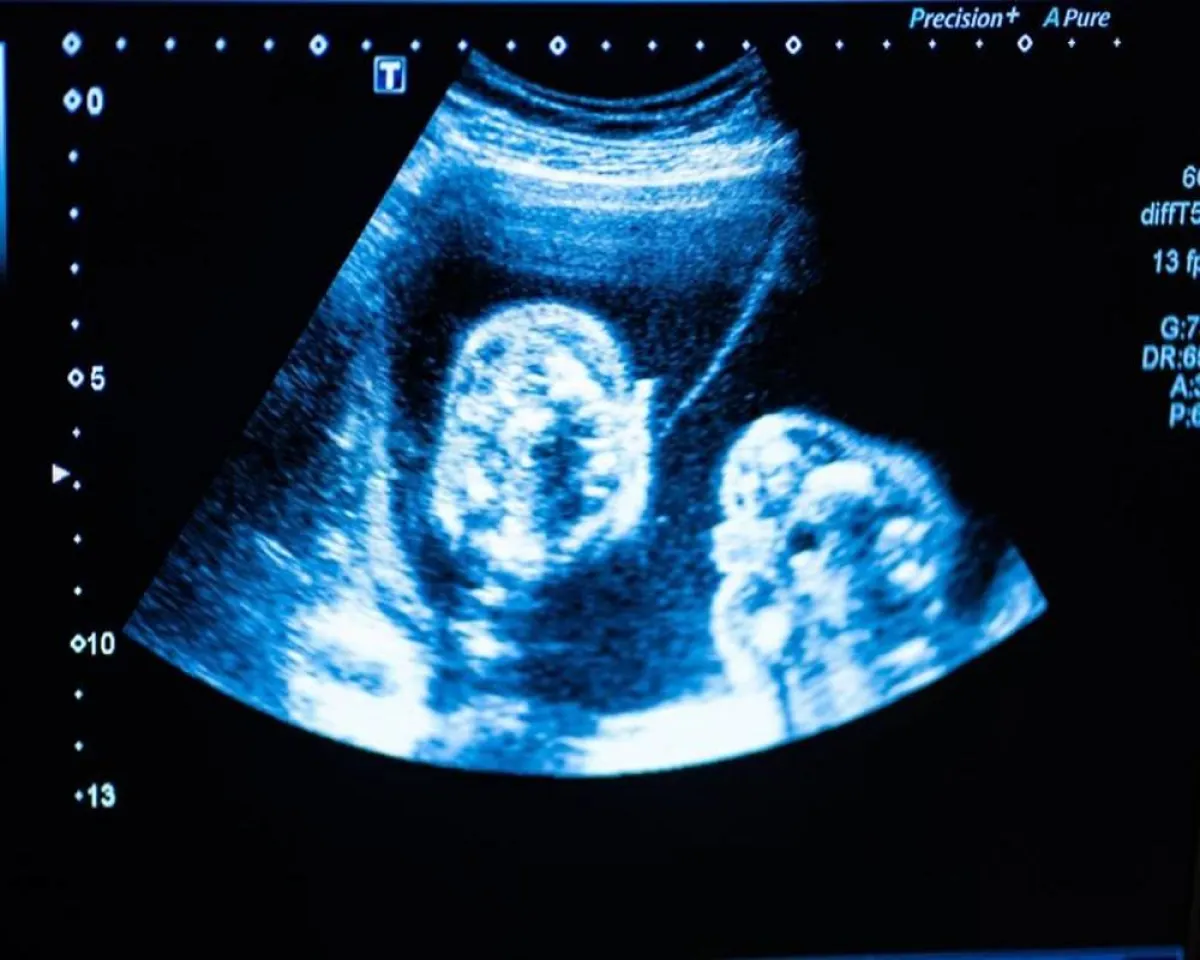

يفضل بعض الآباء الانتظار حتى الولادة لمعرفة نوع طفلهم، بينما يسأل البعض الآخر عند الفحص بالموجات فوق الصوتية الأولى في الشهر الخامس من الحمل عن نوع الجنين.

وفقاً لموقع "momjunction "هناك الكثير من الأساليب المزعومة لمعرفة ذلك، فيمكن أن توفر الاختبارات الطبية إجابة دقيقة، ويمكن أن تشير بعض الطرق المثبتة بالأبحاث والدراسات العلمية إلى علامات الحمل بولد علمياً في وقت مبكر من الحمل.